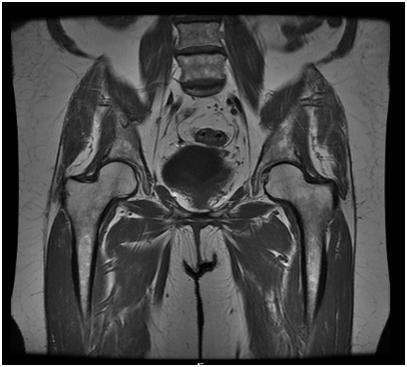

Your doctor has ordered a MRI (Magnetic Resonance Imaging) of your pelvis. MRI uses a magnetic field, radio waves and a computer to create images soft tissues, bones, and internal body structures. MRI of the pelvis allows physicians to examine the pelvic anatomy to rule out any structural abnormalities.

WHAT SHOULD I EXPECT DURING MY EXAM?

- The MRI of the pelvis requires you to lie down on the scanning table, feet first.

- The scanning table will slide your body into the magnet.